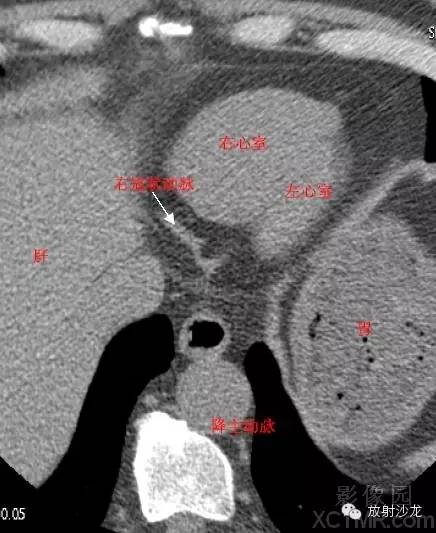

LA -Left Atrium左心房

LV -Left Ventricle左心室

D. Aorta-Descending Aorta降主动脉

LMA -Left Main Artery冠状动脉左主干

LCX -Left Circumflex Artery左回旋支